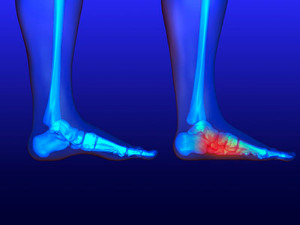

The medical term referred to as a bunion is considered to be a deformity of the big toe. The noticeable symptom is a bony protrusion on the side of the toe, and this typically occurs when the toe points inward. It may produce pain and discomfort as time progresses, in addition to a possible bump forming on the inside of the foot. Patients who are afflicted with bunions may find difficulty in wearing shoes, and may have to select larger shoes that can accommodate this condition. There are reasons why bunions may develop, including genetics which can affect the structure of the foot, and wearing shoes that fit incorrectly or are tight. Some of these types of shoes may include high heels which may not provide adequate room for the toes to move freely. Additionally, enduring an injury may be the cause for a bunion to form. If you notice a bunion beginning to form, it is advised to seek the counsel of a podiatrist who can properly treat this condition.

The medical term referred to as a bunion is considered to be a deformity of the big toe. The noticeable symptom is a bony protrusion on the side of the toe, and this typically occurs when the toe points inward. It may produce pain and discomfort as time progresses, in addition to a possible bump forming on the inside of the foot. Patients who are afflicted with bunions may find difficulty in wearing shoes, and may have to select larger shoes that can accommodate this condition. There are reasons why bunions may develop, including genetics which can affect the structure of the foot, and wearing shoes that fit incorrectly or are tight. Some of these types of shoes may include high heels which may not provide adequate room for the toes to move freely. Additionally, enduring an injury may be the cause for a bunion to form. If you notice a bunion beginning to form, it is advised to seek the counsel of a podiatrist who can properly treat this condition.

Bunions are painful bony bumps that usually develop on the inside of the foot at the joint of the big toe. As the deformity increases over time, it may become painful to walk and wear shoes. Women are more likely to exacerbate existing bunions since they often wear tight, narrow shoes that shift their toes together. Bunion pain can be relieved by wearing wider shoes with enough room for the toes.

- Genetics – some people inherit feet that are more prone to bunion development

- Inflammatory Conditions - rheumatoid arthritis and polio may cause bunion development

In order to diagnose your bunion, your podiatrist may ask about your medical history, symptoms, and general health. Your doctor might also order an x-ray to take a closer look at your feet. Nonsurgical treatment options include orthotics, padding, icing, changes in footwear, and medication. If nonsurgical treatments don’t alleviate your bunion pain, surgery may be necessary.